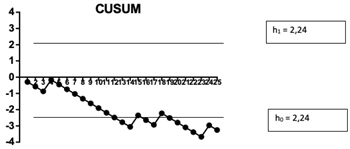

El tipo de test propuesto en nuestro estudio se aplica a conjuntos de datos discretos que toman valores binarios de acuerdo a la ocurrencia o no de un evento (en este caso éxito o fallo de la técnica) y que son recogidos en forma secuencial. La fórmula utilizada en el cálculo del CUSUM se muestra en la Tabla I. La función que define la curva de Cusum en la curva de rendimiento se calcula a partir de las constantes: porcentaje de fallo aceptable (p0) e inaceptable (p1), probabilidad de error Tipo I y II (α y β) a partir de los cuales se calcula el valor de s y los límites de decisión para la hipótesis nula y alternativa h0 y h1 que se mantienen constantes para cualquier valor de la muestra (Tabla I y II). Se tomó como porcentaje de fallo aceptable un 20 % e inaceptable de fallo de 40 % (Tabla II). El error α y β se tomó como 0,1.

Para cada éxito el valor de s se resta al valor de CUSUM previo y para cada fallo el valor de 1-s se suma al valor previo, por lo cual este aumenta con los sucesivos fallos, indicando el ascenso de la curva una tendencia al fracaso y desciende con los éxitos indicando un desempeño óptimo.

Cuando la curva de CUSUM cruza la línea de decisión h0 el porcentaje de fallo no diferirá estadísticamente de la frecuencia aceptable de este, por lo que se acepta la hipótesis nula con un error tipo II igual a β. Si la curva cruza la línea de decisión h1 entonces el porcentaje de fallo verdadero es significativamente más alto que el porcentaje de fallo aceptable (h1) con un error tipo I igual a α. Mientras no se alcance ninguno de los dos niveles de decisión no puede hacerse ninguna inferencia estadística que permita conclusión alguna y debe analizarse un número mayor de observaciones.

Entre agosto y diciembre de 2020, 25 pacientes fueron reclutados, 15 de sexo femenino y 10 de sexo masculino. La edad promedio de los mismos fue de 52 ± 12 años. Ocho de ellos presentaron canal estrecho lumbosacro y 17 protrusiones discales en los espacios L4-L5 y L5-S1. En 6 pacientes la inyección epidural se realizó en el espacio L4-L5 y en los restantes a nivel de L5-S1. La distancia promedio desde la piel al complejo posterior evaluada por el escaneo ecográfico previo al procedimiento fue de 6,4 ± 1,5 cm. De los 25 procedimientos realizados, en 21 se alcanzó a detectar el espacio epidural sin ayuda de la fluoroscopia, en un tiempo promedio de 5 ± 1,6 minutos. Esto implica una tasa de éxito del 84 %. En los cuatro procedimientos restantes el espacio epidural fue alcanzado con éxito mediante el uso complementario de la fluoroscopia. De los 21 procedimientos catalogados como exitosos, en 20 el contraste alcanzó el espacio epidural anterior (95 %) y en 19 (90 %) se registró dolor o parestesias en el miembro inferior correspondiente al dolor radicular. En un caso se registró dolor contralateral. En los cuatro procedimientos restantes el espacio epidural fue alcanzado con éxito mediante el uso complementario de la fluoroscopia. La Figura 3 muestra la curva de desempeño utilizando el método de la Suma Acumulada (CUSUM). Como puede observarse en la misma, la banda de decisión h0 fue cruzada después de 12 procedimientos, y se mantuvo de ese modo hasta el procedimiento número 15.

Fig. 3. Curva de aprendizaje del investigador principal, de la inyección epidural interlaminar de esteroides, ecoguiado, en eje corto y en plano, utilizando el método de la Suma Acumulativa (CUSUM). Se observa que después de 12 procedimientos, la curva se cruza la banda de decisión H0, lo que representa que se obtuvo un índice de éxito del 80 % con una probabilidad menor del 10 % que dicho índice se deba al azar.